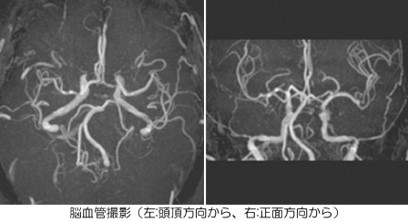

MRA.jpgMRIは、特殊な処理で造影剤を使用しなくても

血管の状態を知ることができます。

カテーテル検査などでしか分からなかった、脳の

動脈瘤や血管の狭窄も安全に診断が可能です。